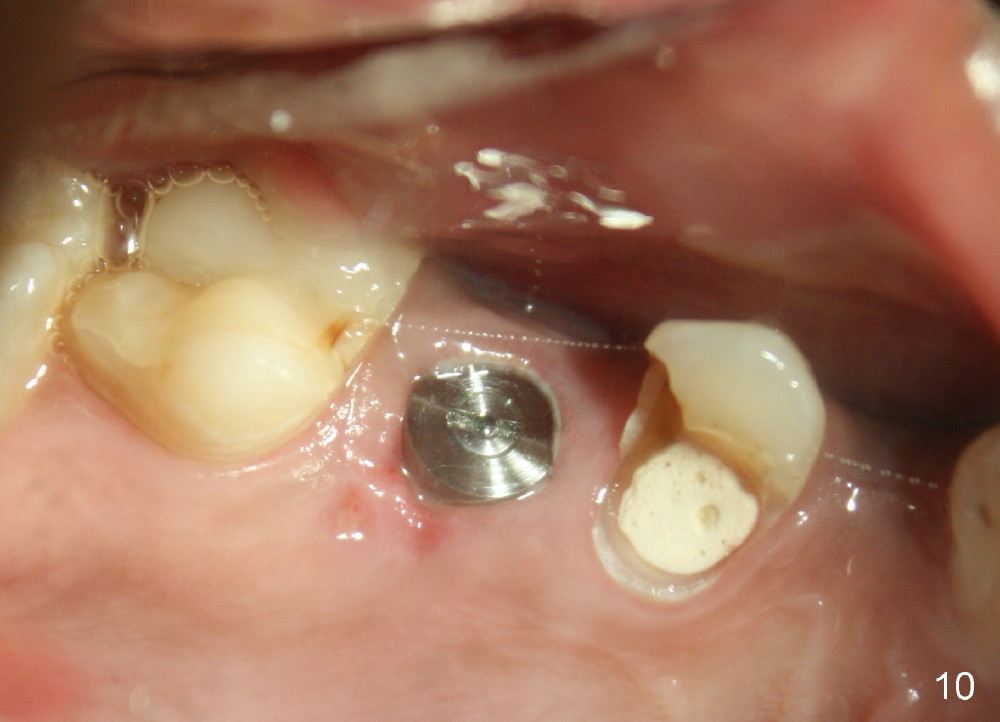

In addition to pain associated with dry socket, the buccal plate is atrophic 10 months post extraction (Fig.7 arrowheads, 1st case). A smaller implant (6x17 mm) is placed after bone expansion (Fig.8, bone appears to be soft). The buccal plate morphology improves immediately (Fig.9) and 6 days (Fig.10) post implantation and bone expansion. The patient returns for follow up 7 months postop; the implant appears to have osteointegrated (Fig.11). The implant has been restored for 3 months (09/11/2014).